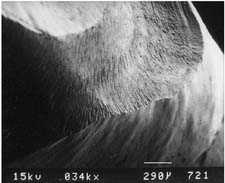

Table 7-3 MARGINS PRODUCED BY VARIOUS TYPES OF BURS

| Bur appearance | Low magnification of the prepared margin | High magnification of the prepared margin |

|---|---|---|

| CHAMFERS | ||

| Chamfer carbide (high speed) | ||

![]() |

| Finishing carbide (high speed) | ||

| Finishing carbide (low speed) | ||

| Chamfer diamond coarse (high speed) | ||

| Fine diamond (high speed) | ||

| Chamfer diamond fine (low speed) | ||

| SHOULDERS | ||

| Cross-cut fissure (high speed) | ||

| Cross-cut fissure (high speed) and hoe | ||

| Cross-cut fissure carbide (high speed) | ||

| Flat-end coarse diamond (high speed) | ||

| Flat-end coarse diamond (high speed) and hoe | ||

| Fine grit diamond (high speed) | ||

| Fine grit diamond (low speed) | ||

Courtesy of Dr. H. Lin.